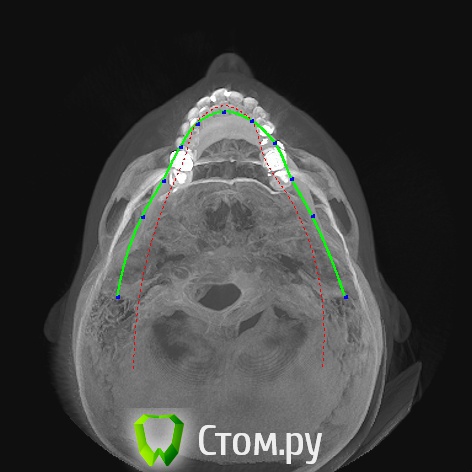

Гуля-Р Опубликовано 1 ноября, 2014 Поделиться Опубликовано 1 ноября, 2014 Добрый день! Ортодонт настаивает на удалении нижних центральных резцов, а не четверок, т.к. для корни нижних резцов подвержены резорбции. Если удалить четверки, то центральные резцы потом расшатаются и надо будет ставить импланты. Удаление резцов приведет к нарушению дикции, да и вид нижних зубов - 2 резца и сразу клыки - не хочется. Как думаете, есть ли шанс, что не потеряю резцы? Пока настроена на удаление четверок, но еще не могу решить. Когда я спросила, тогда расшатаются все 4 нижних резца, ведь корни с резобцией у всех этих резцов, ортодонт ответил, что 2 других резца будут двигать очень медленно и сохранят зубы. Может все 4 резца можно медленно раздвинуть... а потом как-то закрепить ... типа шинирования... Очень нужен совет, извелась вся. Ссылка на комментарий

Фазлиев Азат Ильдусович Опубликовано 7 ноября, 2014 Поделиться Опубликовано 7 ноября, 2014 Улыбнуться на 6 зубов не получилось, даже помогая пальцами.Внизу вообще без удаления! Только сепарация по необходимости. Ссылка на комментарий

Гуля-Р Опубликовано 9 ноября, 2014 Автор Поделиться Опубликовано 9 ноября, 2014 (изменено) Ну все... нижние центральные резцы отстояла под расписку о том, что в курсе о резорбции и последствиях, удалили нижние четверки, теперь мои скученные зубы долны поместиться в ряд, тем более что удалила внизу единственную восьмерку. Надеюсь не испугаюсь в дальнейшем хирургического вмешательства. В любом случае, зубы должны стать ровнее. Спасибо за ответы. Они помогли мне сделать выбор и не удалить резцы. Изменено 9 ноября, 2014 пользователем Гуля-Р Ссылка на комментарий